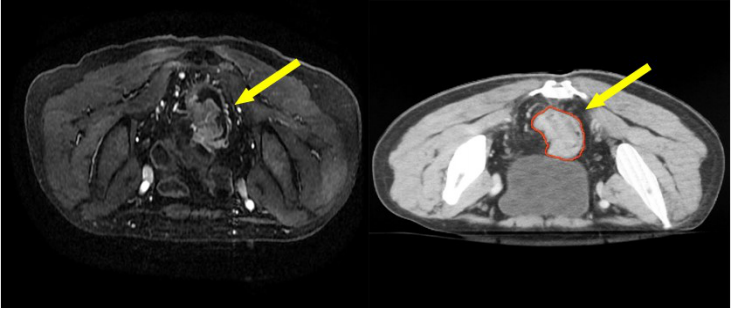

• European?Radiology:基于深度學習的三維超分辨率MRI放射組學模型對直腸癌術前T分期的預測

European?Radiology:基于深度學習的三維超分辨率MRI放射組學模型對直腸癌術前T分期的預測

目前,結直腸癌在全球腫瘤發病率和死亡譜中分別排名第三和第二。直腸癌(RC)占結直腸癌的1/3,在東亞的發病率最高。盡管根治性手術仍然是唯一的治愈方法,但基于治療前分期的新輔助化療(nCRT)的實施提高了R0的切除率,并進一步改善了局部腫瘤的控制。nCRT被推薦為局部晚期RC(LARC)患者(T3/4和/或N+)的標準療法,而對于早期患者(T1/2和N-)則沒